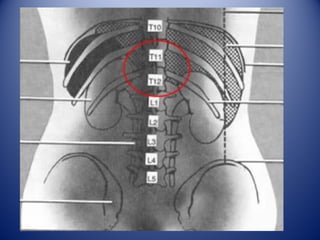

Situados a ambos lados

de la columna vertebral

a la altura de las 2

últimas vértebras

torácicas y las 2 primeras

vértebras lumbares.

Pared posterior del abdomen

Detrás del peritoneo (retroperi-

toneo) y por delante de la 11 y 12

Costillas.

Aquí podemos apreciar

la proyección de los

riñones en la pared

posterior.